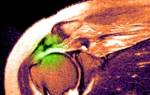

Вывих — это состояние, при котором суставные поверхности смещаются относительно друг друга.

Нормальная работа сустава возможна, если суставные поверхности костей конгруэнтны, то есть их формы соответствуют. При вывихе кости расходятся, конгруэнтность теряется, и движение в суставе становится невозможным. Вывих характеризуется стойким и полным смещением: стойким, потому что сместившиеся кости не возвращаются в исходное положение, и полным, так как поверхности, которые должны соприкасаться, не соприкасаются даже частично. Обычно при вывихе разрывается капсула сустава, и одна из суставных поверхностей выходит через этот разрыв. Если смещение частичное, это состояние называется подвывихом.